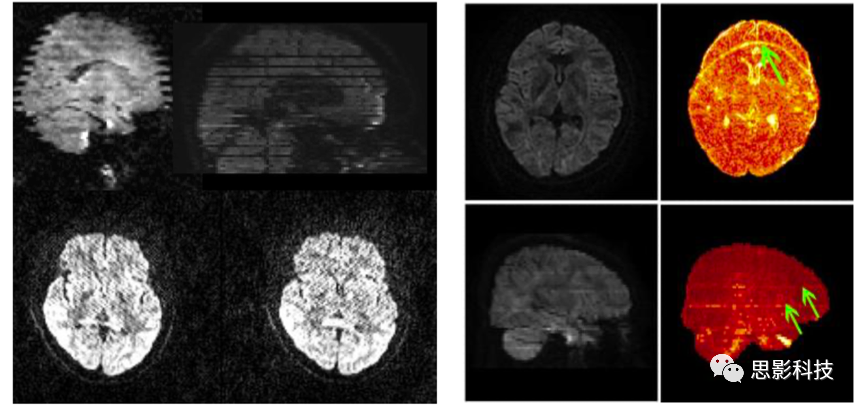

圖例:不同偽影示意圖

主要包括:掃描參數(shù)檢查,包括TR、體素大小、掃描時(shí)長(zhǎng)等參數(shù),確保參數(shù)合適與統(tǒng)一;圖像偽跡檢查,包括鬼影、變形等;其他檢查,包括頭動(dòng)狀況、圖像是否缺損等。對(duì)于可能發(fā)現(xiàn)的數(shù)據(jù)質(zhì)量問(wèn)題,思影將提供合適的參考意見(jiàn)。也可幫助客戶(hù)進(jìn)行掃描參數(shù)的設(shè)計(jì)。